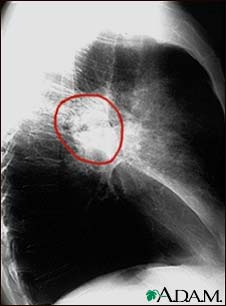

A lateral view of a chest x-ray in a patient with central cancer of the lung.